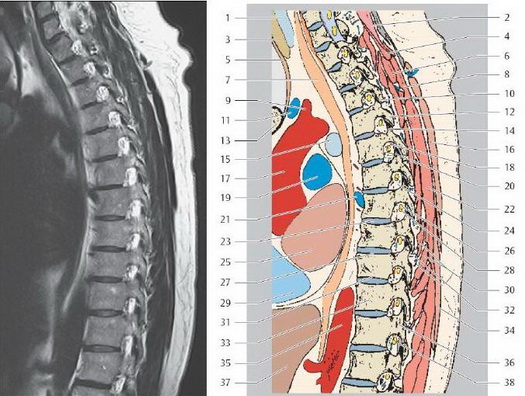

МРТ грудного отдела позвоночника

1. Трахея

2. Ременная мышца шеи

3. Щитовидная железа

4. Полуостистая мышца головы

5. Грудиноподъязычная мышца

6. Задняя верхняя зубчатая мышца

7. Пищевод

8. Большая ромбовидная мышца

9. Плечеголовной ствол

10. Межпозвонковый сустав ТЗ/Т4

11. Левая плечеголовная вена

12. Нижний суставной отросток Т4

13. Грудина (рукоятка)

14. Верхний суставной отросток Т5

15. Левый главный бронх

16. Трапециевидная мышца

17. Восходящая аорта

18. Задняя межреберная артерия

19. Легочная артерия

20. Межпозвонковая вена

21. Полунепарная вена

22. Мышца, выпрямляющая туловище

23. Межпозвоночный диск Т7/Т8

24. Межпозвоночное отверстие

25. Левое предсердие

26. Спинномозговой узел (дорзальный корешок)

27. Верхняя концевая пластинка позвонка Т

28. Спинномозговой узел (вентральный корешок)

29. Правое предсердие

30. Многораздельная н полу остистая мышцы груди

31. Нижняя концевая пластинка позвонка

32. Заднее наружное позвоночное венозное сплетение

33. Тело грудного позвонка

34. Широчайшая мышца спины

35. Нисходящая аорта

36. Ножка дуги позвонка

37. Печень

38. Желтая связка

МРТ поясничного отдела позвоночника